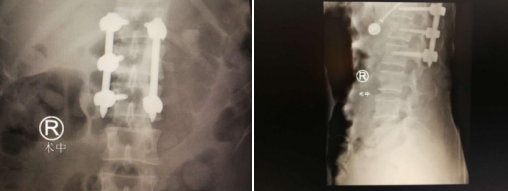

术中

这次机器人辅助手术中,先由C型臂对患者进行三维影像扫描,图像被同步传输至手术机器人系统。医生在导航系统屏幕上设计好钉道,机器人的机械臂将手术工具精确定位到手术位置,套筒指向目的钉道的进钉点,从而实现螺钉的精准安全植入。手术很顺利。以往这类手术,患者手术伤口约有20厘米,现在只是几个不到1厘米的小切口;出血量也由以往的五六百毫升降低到30毫升;且基本不造成患者肌肉软组织损伤,手术时间缩短了50%以上。从手术效果来看,传统手术后一般需要卧床休息3个月左右,而此次术后几天,患者已经能正常下地行走,且患者的骨折复位效果理想、固定稳定。

随后,手术小组又为患者进行了左股骨髁上骨牵引术,顺利完成。